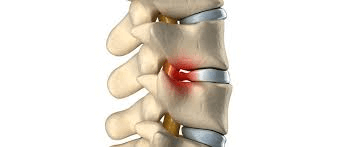

지난회에 이어서 척추원반탈출증의 원인은 대부분 세월이 지나면서 반복된 사용으로 인한 서서히 발생하는 Wear & Tear로 인한 퇴행성 디스크 병화로 발생합니다. […]

척추를 구성하는 24개 척추뼈 사이에 위치하는 마치 고무같은 완충제 역할을 하는 척추원반(디스크)에 문제가 생긴 것을 의미합니다. 디스크는 부드러우면서 젤리같은 중심체(Nucleus)와 […]

허리 통증으로 2년전에 척추협착증(Spinal Stenosis) 진단을 받았으나 다행히 척추수술을 안받고 몇번의 재활치료로 증세가 호전되어 큰 문제없이 생활하다가 최근 심한 허리통증과 […]